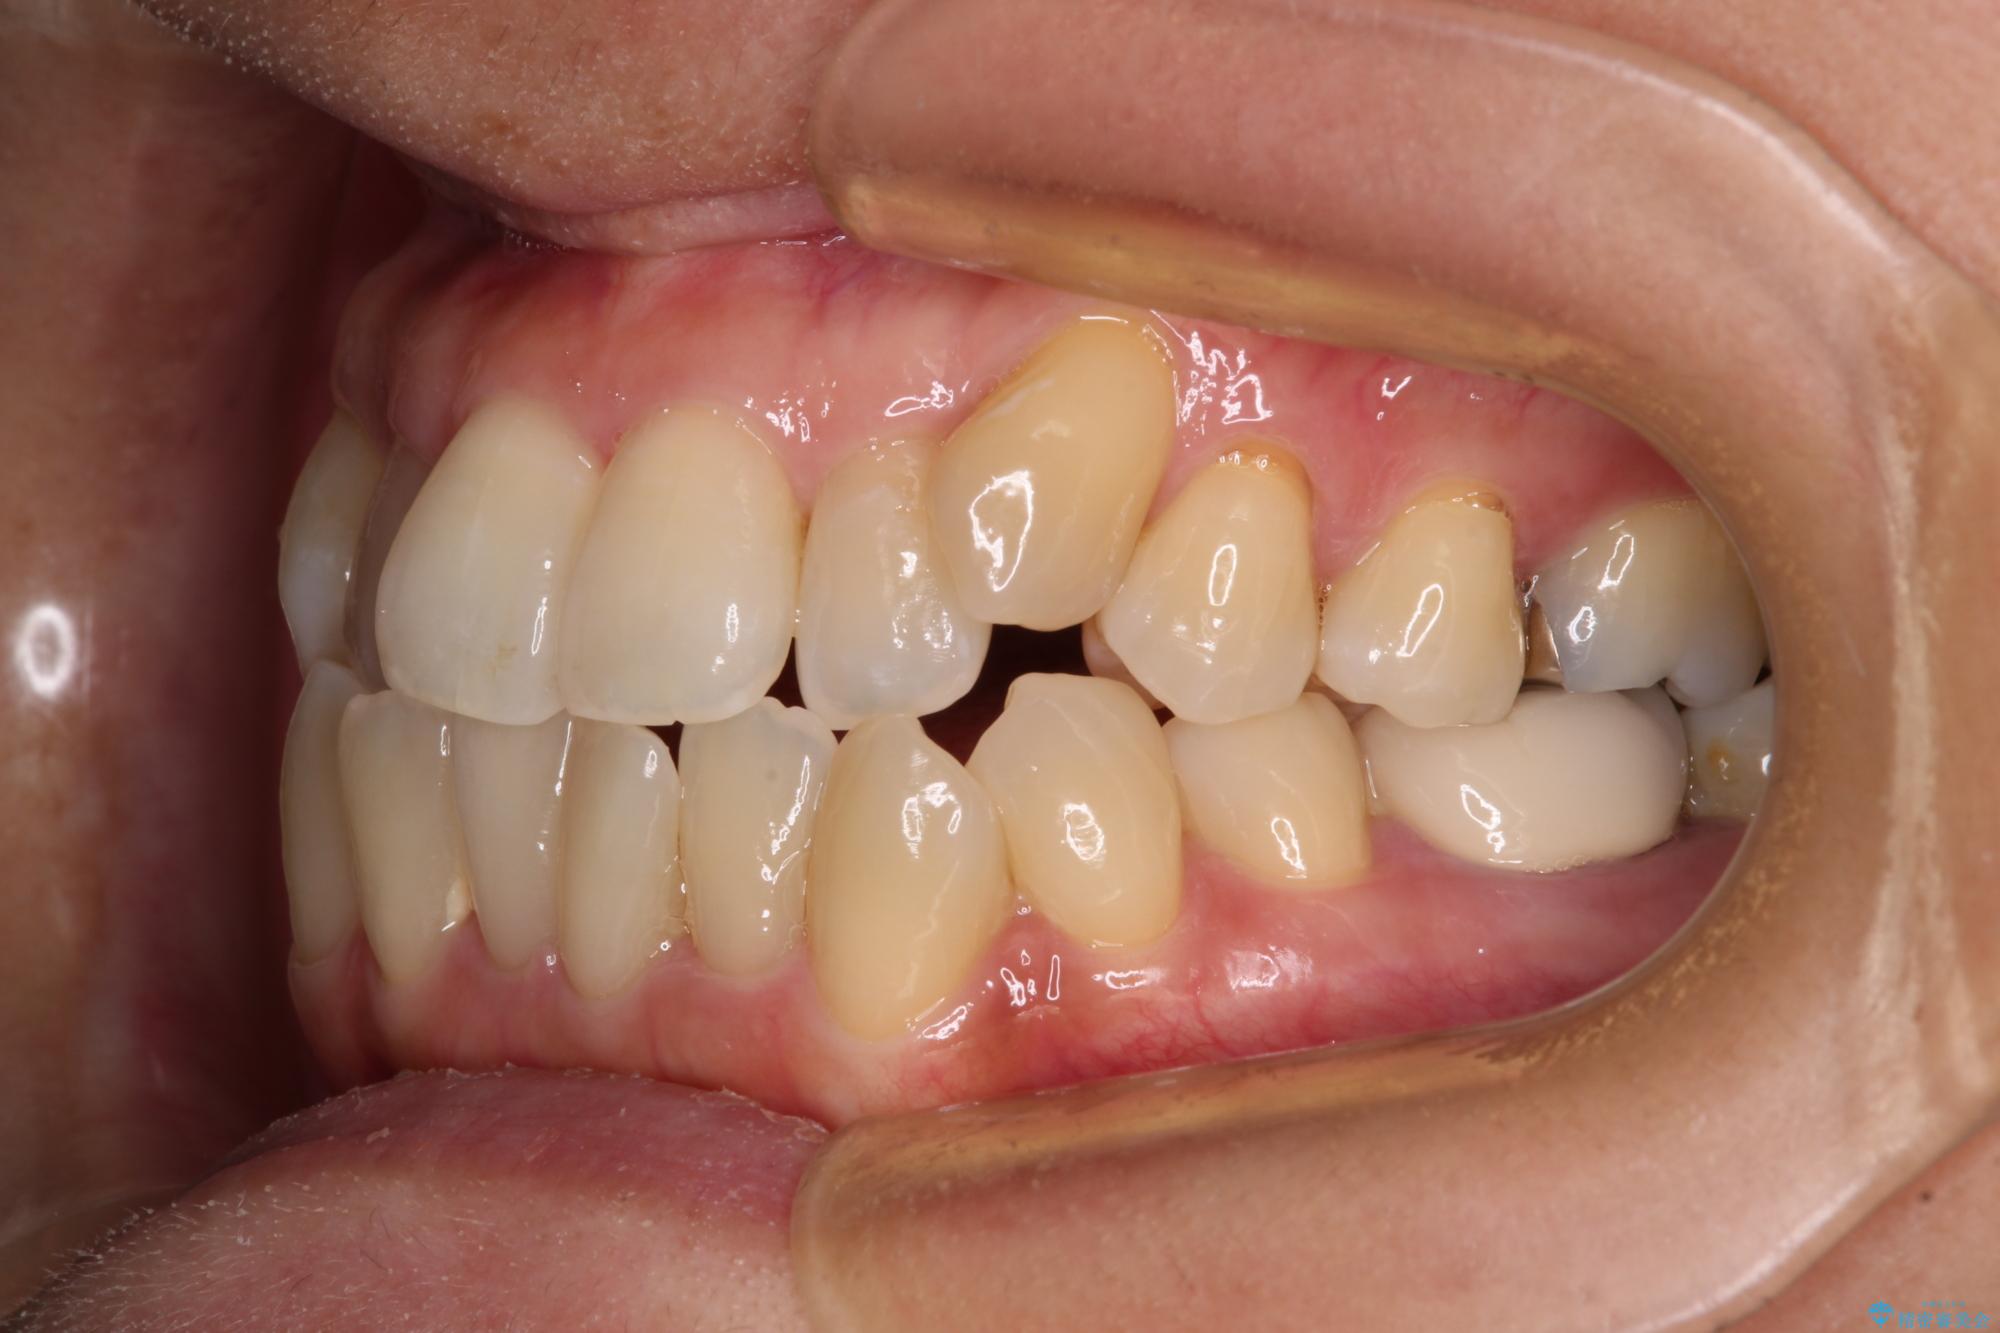

- 前歯のデコボコや八重歯を治したいとのことで来院された患者様です。

受け口傾向の骨格であり、前歯はクロスバイトまたは切端咬合となっており、下顎を中心に歯列全体の後方移動を行い、IPR(歯と歯の間を削る)によってデコボコが解消するように設計し、インビザラインにより治療を行うこととしました。

受け口傾向のインビザライン矯正は比較的治療を行いやすいため、きれいに仕上げることができました。舌の突出癖が顕著であったため、改善のためのトレーニングをしっかりと行っていただきました。